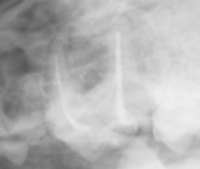

画像の丸で囲ってある部分に破折したファイルが認められます。

かなり削りましたが、この状態で初めて破折ファイルを目視することが可能となります。レントゲンではわかりやすいのですが、およそ0.5~0.8mmを見ることが可能です。

少しづつ超音波などで周辺を掘削しファイルを動揺させます。

無事に摘出し新たなファイルを入れた状態です。

それでは今回入れたファイルと以前ファイルを入れられた状態の角度を比較するために画像を重ねて表示してみましょう。

正しくファイルを入れた方向と最初にファイルを破折させた角度を見ると、折れたファイルはかなじ前方から根管口に入っていることがわかります。このような現象は、最初に根管へアクセスする際、歯をあまり削らずに行おうとしたために、急角度にファイルが曲がって根管口へ突入したために破折したことがわかります。下記に示すように、青でファイルを挿入すると折れますが、黄色の位置から挿入すると折れることはありません。根管に対してできる限りまっすぐにいれることのできるアクセスを行うことが重要です。